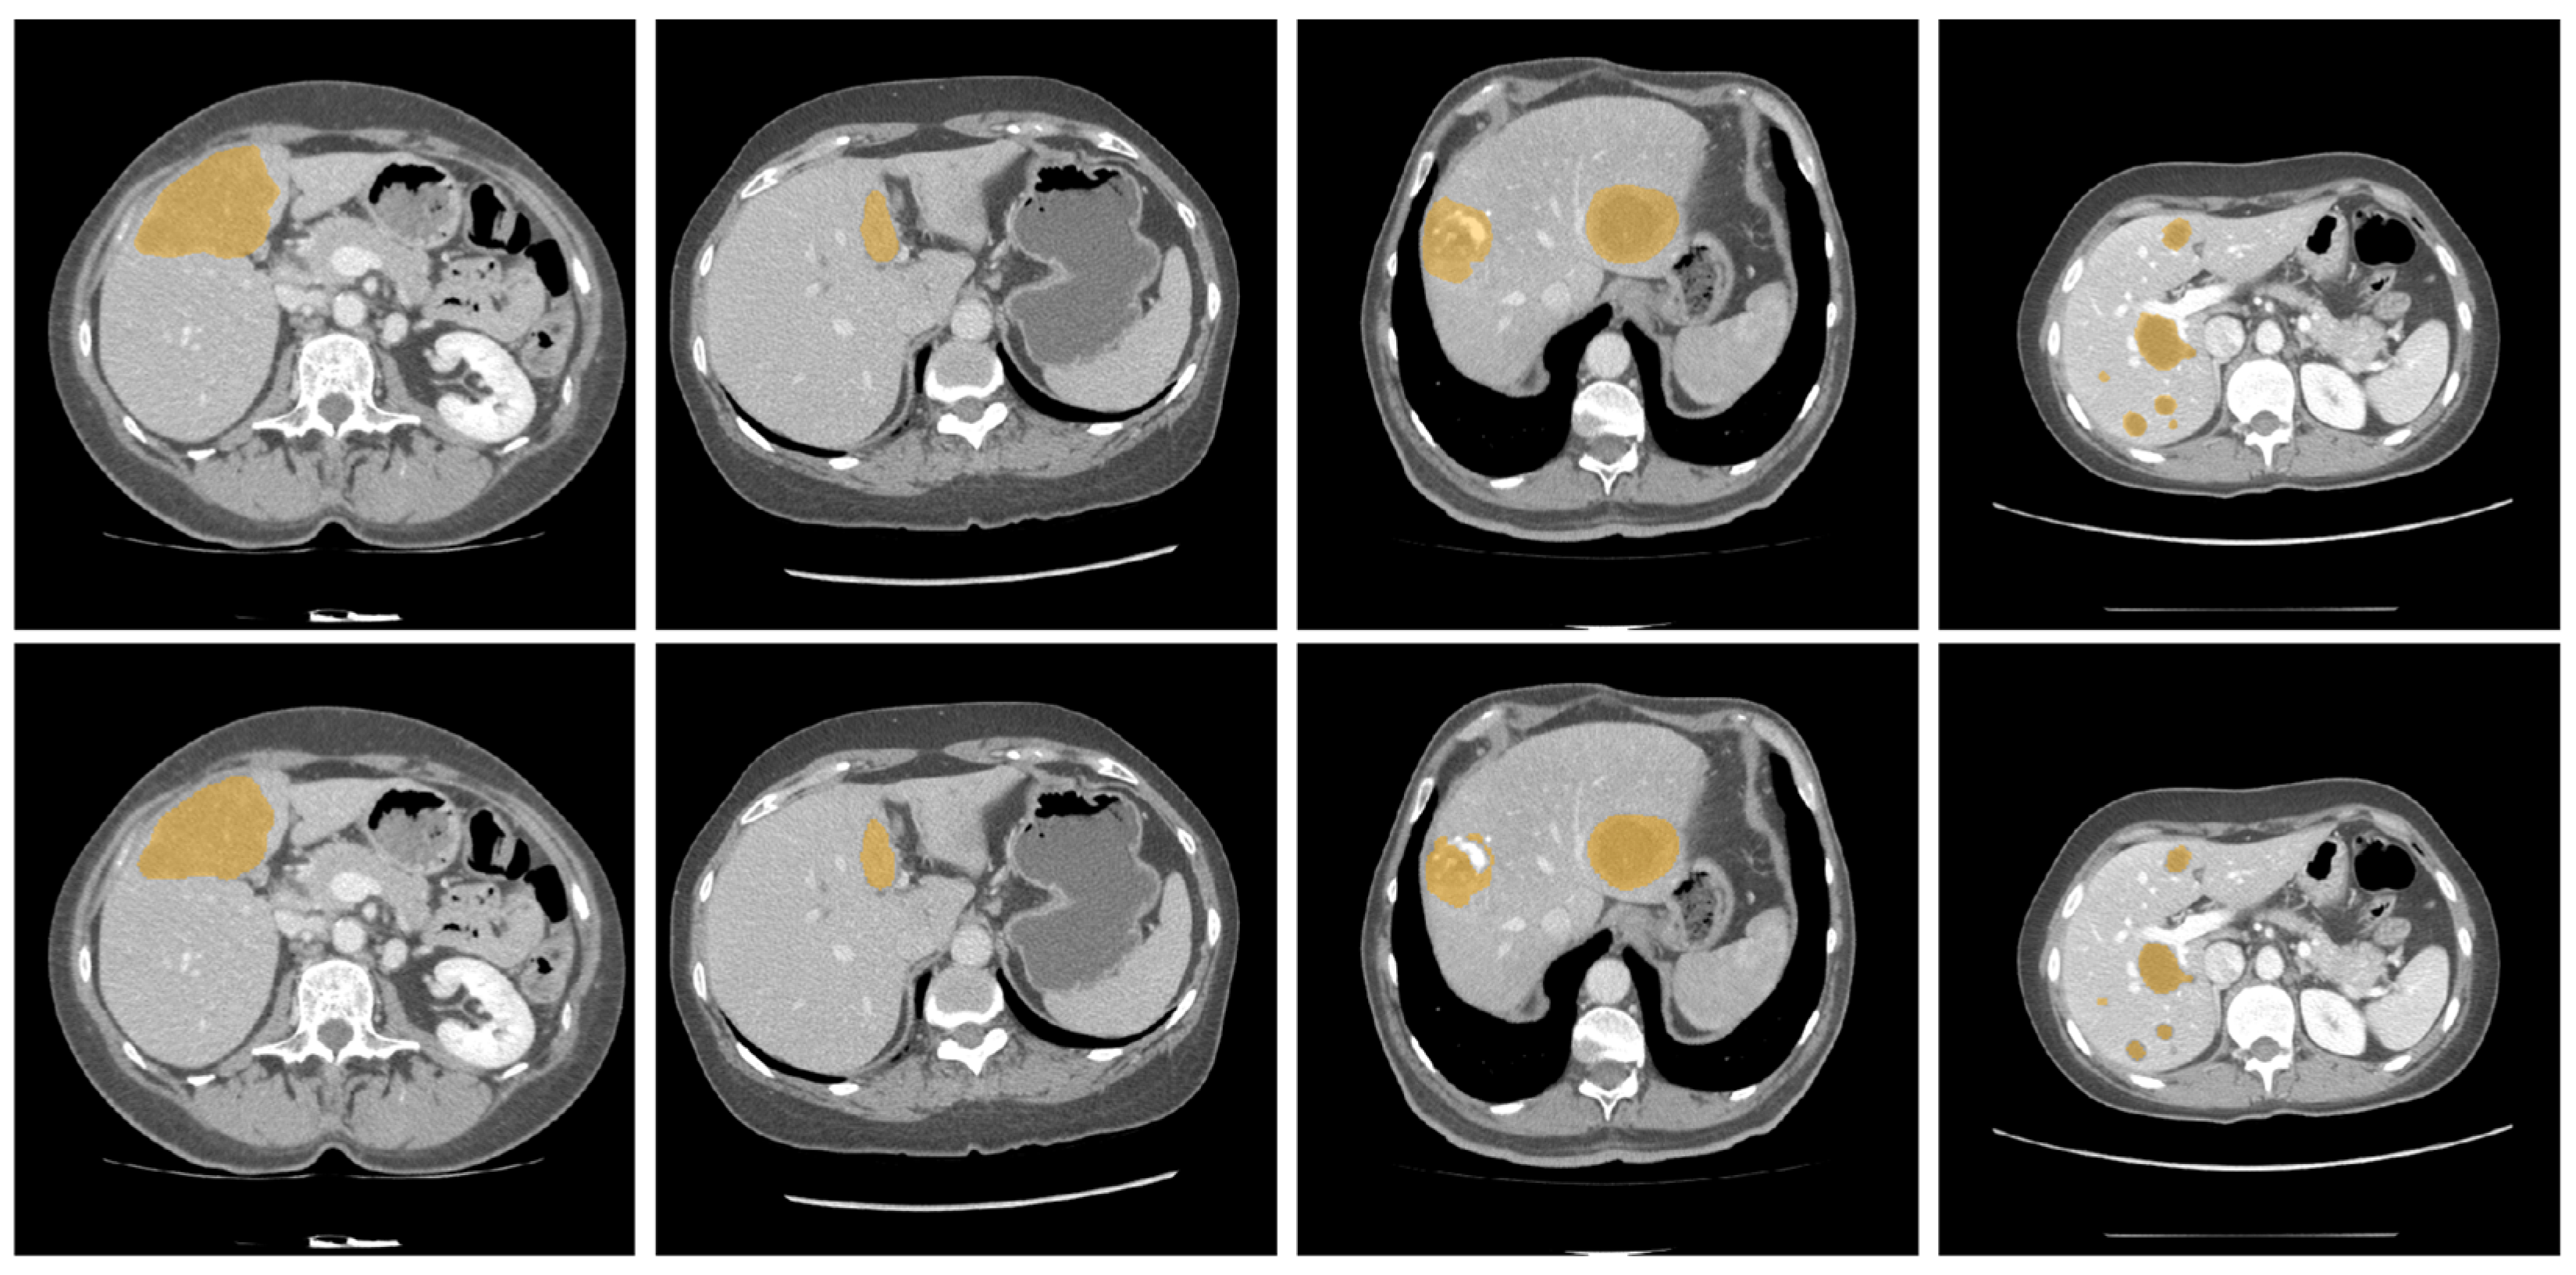

Figure 4 and Figure 5 illustrate some examples of the liver tumor segmentation results with our model from the LiTS dataset and the 3DIRCADb dataset, respectively. Visual inspection of the segmentation results reveals that the predicted tumor regions are properly aligned with the ground truth in terms of both the number of tumors and their morphology.

Figure 5. Examples of tumor segmentation results of the proposed model over the 3DIRCADb dataset. Upper: the ground truth; bottom: the predicted tumor regions.